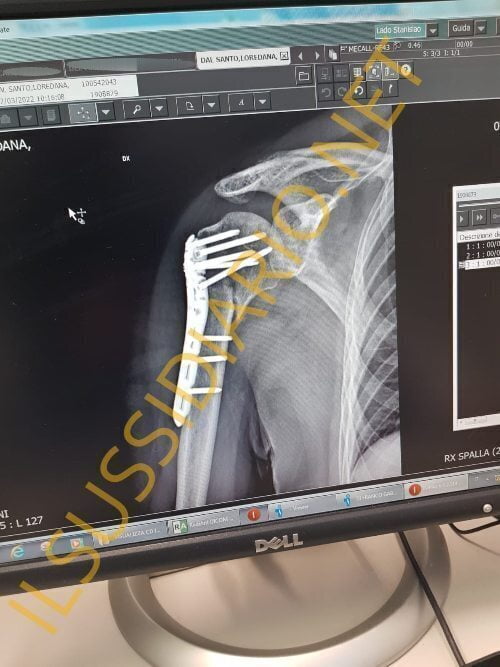

L’intervento al quale si è sottoposta Lory Del Santo per curare la frattura alla spalla poco prima della sua partecipazione all’Isola dei Famosi, ha necessitato l’inserimento di placche e chiodi. E’ questo il principale motivo per il quale, una volta in Honduras, la regista ed attrice non ha potuto sottoporsi a prove fisiche importanti, per non compromettere l’esito dell’operazione alla quale si è sottoposta.

Dalle foto relative al post operazione di Lory Del Santo è possibile notare la ferita piuttosto importante che parte dalla spalla e si estende lungo la parte alta del braccio e per la quale sono stati necessari diversi punti di sutura. Nel corso della sua partecipazione all’Isola, tuttavia, la regista ha preferito non citare mai l’incidente di cui è stata vittima poco prima della sua partenza ma soprattutto è stata l’unica naufraga a non recarsi mai in infermeria, a dispetto di quanto accaduto con alcuni suoi compagni di avventura, ‘rei’ di aver approfittato di un controllo medico per potersi rifocillare.